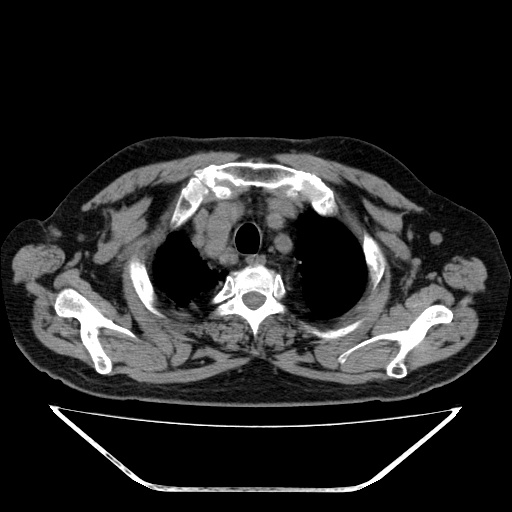

另胸椎旁改变考虑神经鞘瘤可能性大

1双肺转移性肺癌,2t12~l1右侧椎旁神经鞘瘤。

双肺多发转移瘤。纵隔淋巴结肿大。胸椎右旁软组织结节,考虑神经源性肿瘤,请进一步检查。

胸椎旁软组织密度影,与椎管内结构相连,相应椎间孔开大,考虑为神经源性肿瘤(神经鞘瘤)可能

1双肺及纵隔淋巴转移性病变,2t12~l1右侧椎旁神经鞘瘤。

支持 1、双肺转移瘤伴纵隔淋巴结肿大 2、右侧椎旁神经鞘瘤可能性大

胸椎右旁软组织结节,考虑神经源性肿瘤。